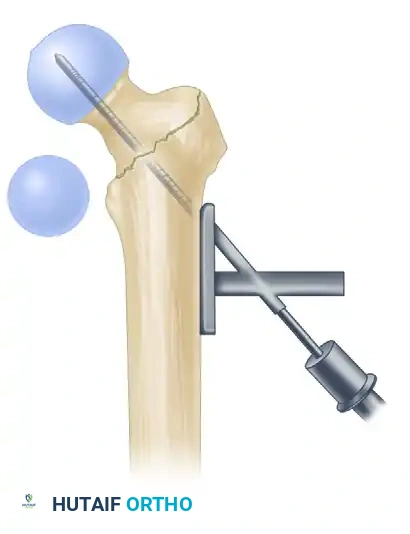

Fracture Reduction

Closed reduction must be achieved prior to prepping. Apply longitudinal traction to restore length, followed by internal rotation (typically 10 to 15 degrees) to correct the external rotation deformity and profile the femoral neck accurately on the AP view. Evaluate the reduction fluoroscopically. If closed reduction is unacceptable, percutaneous adjuncts (e.g., a ball-spike pusher, collinear reduction clamps, or a Schanz pin in the proximal fragment) or a formal open reduction must be utilized.

1. The Modified Medial Trochanteric Entry Portal

For the fixation of intertrochanteric femoral fractures, the selection of the entry portal is arguably the most critical step of the operation. We advocate for the modified medial trochanteric portal.

Anatomical Landmarks: The modified medial trochanteric portal is located on the medial aspect of the greater trochanter, directly along the trochanteric ridge on the AP view, and perfectly in line with the central axis of the femoral shaft on the lateral view.

2. Incision and Guide Pin Placement

- Localize the entry point with a guide pin on the medial aspect of the greater trochanter.

- Insert the guide pin 2 to 3 cm distally into the proximal fragment.

At this juncture, utilize fluoroscopy to rigorously assess the guide pin placement in both AP and lateral planes.